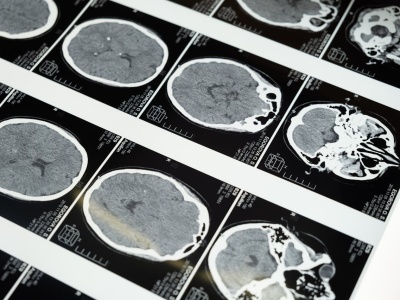

Glejaki to najczęstsze i najbardziej agresywne guzy mózgu. Co zawiera nowy raport KRN? Artykuł Glejaki wciąż wyzwaniem. Raport KRN pokazuje skalę problemu w Polsce pochodzi z serwisu Alert Medyczny.